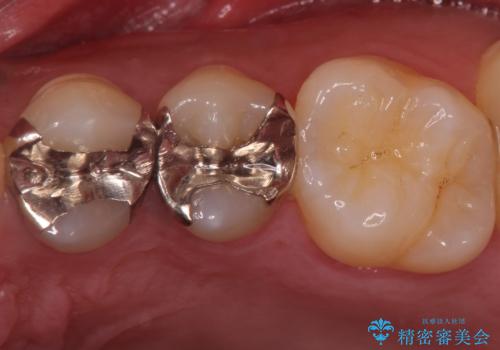

- 右上6 セラミックインレー 77,000円費用は治療当時の料金となります

小さな段差もないような適合の良い修復物は他の修復物に比べて今後の虫歯リスクを抑えることができます。